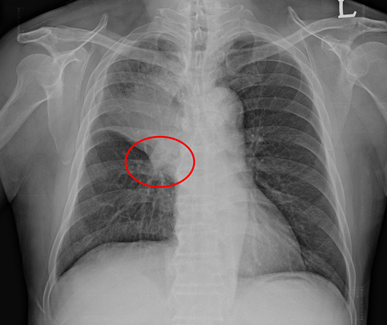

Reverse S Sign Of Golden

Golden S Sign